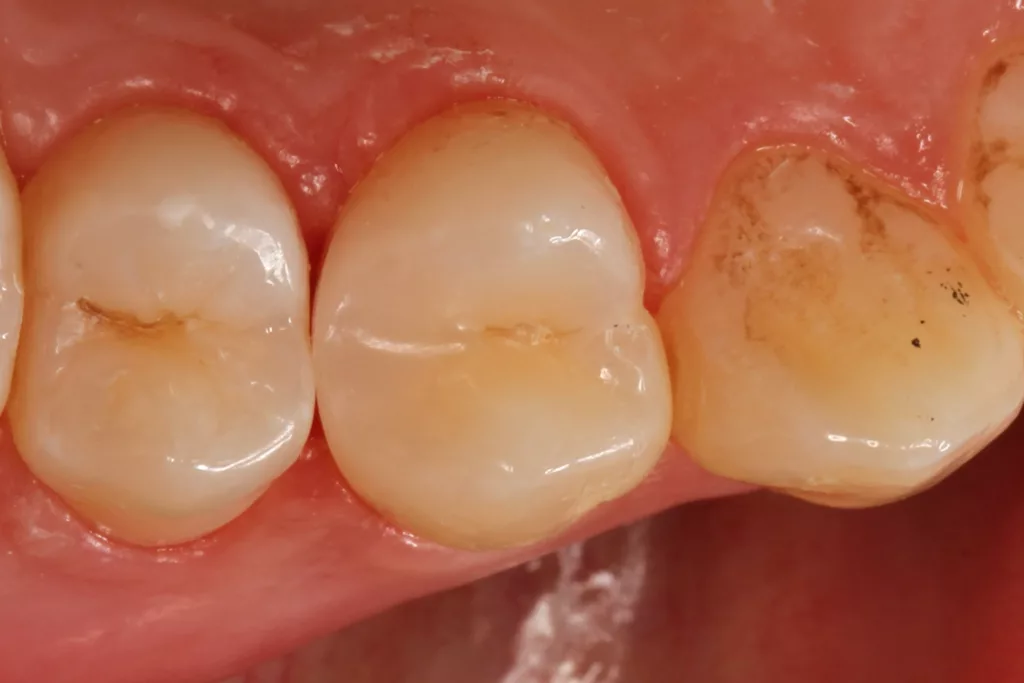

Fall 2: Versorgung einer Initialkaries an Zahn 14 und später an 15

Die 26 Jahre alte Patientin störte sich an der approximalen Lücke zwischen den Zähnen 14 und 15, da sich hier ständig Speisereste impaktierten. Bei der klinischen Inspektion fiel die Initialkaries distal an Zahn 14 auf (Abb. 7). Die Patientin wurde dahingehend beraten, den Spalt mit einer minimalinvasiven Kompositrestauration zu versorgen – bei zeitgleicher Exkavation der Karies an Zahn 14. Nach Exkavation und Präparation des Defektes (der sich als deutlich ausgeprägter präsentierte als anfangs angenommen) erfolgte identisch zu Fall 2 die Ausformung der Kavität mit einer Teilmatrize (Danville ultra thin flex), einem Kunststoffkeilchen (G-Wedge) und der Separation mit einem NiTin-Prämolaren-Spannring (re-invent, Abb. 8).